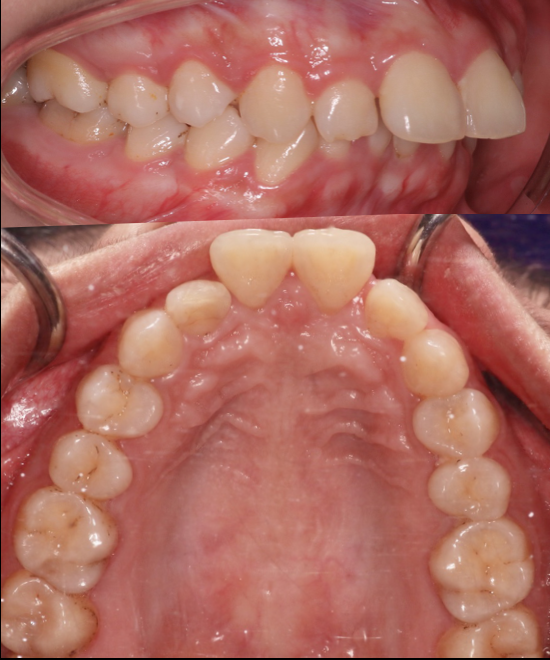

BRACES - IMPACTED CANINE

This patient presented with an impacted upper right canine. Through precise orthodontic treatment, the tooth was successfully guided into its correct occlusal position. The full case was completed in just 16 months, resulting in a well-aligned, functional, and esthetically pleasing smile — expertly treated at Moral Dental Clinic.